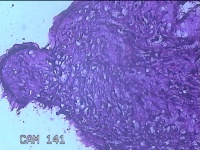

左大腿内侧包块

性别

男

年龄

21岁

临床诊断

脂肪瘤

一般病史

左大腿内侧起包块一月余。

标本名称

大体所见

灰白暗红色包块2.5x2x0.8cm一个,表面糜烂,切开包块呈实性,切面灰白暗红色,质软。